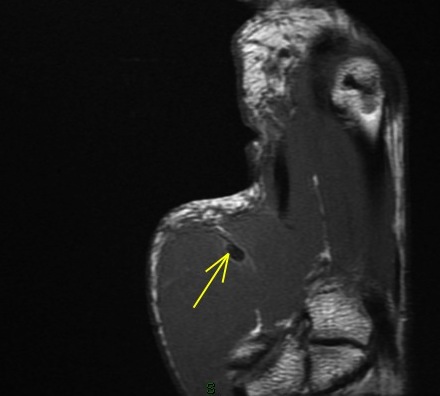

Figure 4 for case Flexor pollicis longus tendon ( RID2383 ) laceration

Figure 4